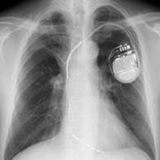

2.植え込み型除細動器(ICD)とは?

心室細動や心室頻拍などいわゆる致死性不整脈が生じた場合、直流通電のみが唯一信頼できる治療手段です。

一度致死的不整脈を起こされた方、今後致死的不整脈が発生する可能性が高い方には、除細動器を左前胸部に植え込み、突然死を回避することが可能です。(図5)